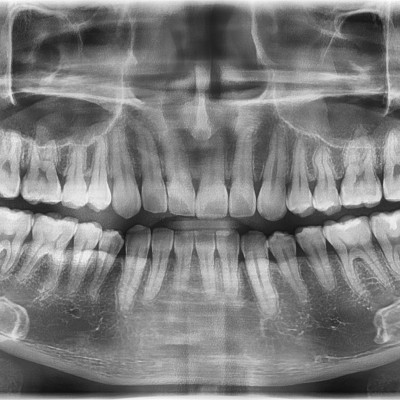

#38 사랑니 발치 N새글 #38 사랑니 발치 구강 외과 전문의가 당일 발치했습니다. -----------------------------..